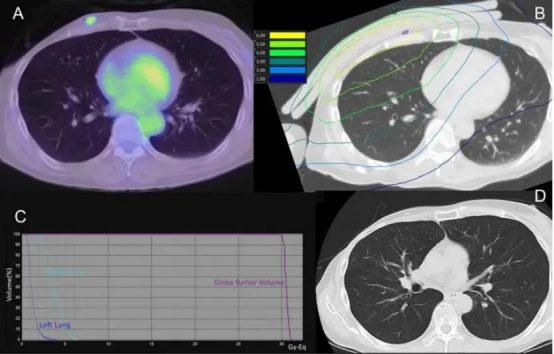

在日本江户川医院开展的一项临床研究中,一位72岁的乳腺癌胸壁复发患者接受了BNCT治疗。治疗前,PET-CT显示胸壁病灶代谢活跃;治疗6个月后,同一部位代谢显著降低,肿瘤明显缩小。

(A)硼中子俘获疗法(BNCT)肺部剂量分布图(紫色区域代表肿瘤大体靶区GTV);(B)治疗后90天的CT影像(未显示放射性肺炎迹象);(C)治疗前的弥散加权MRI影像;(D)治疗后90天的MRI影像(显示信号强度降低)